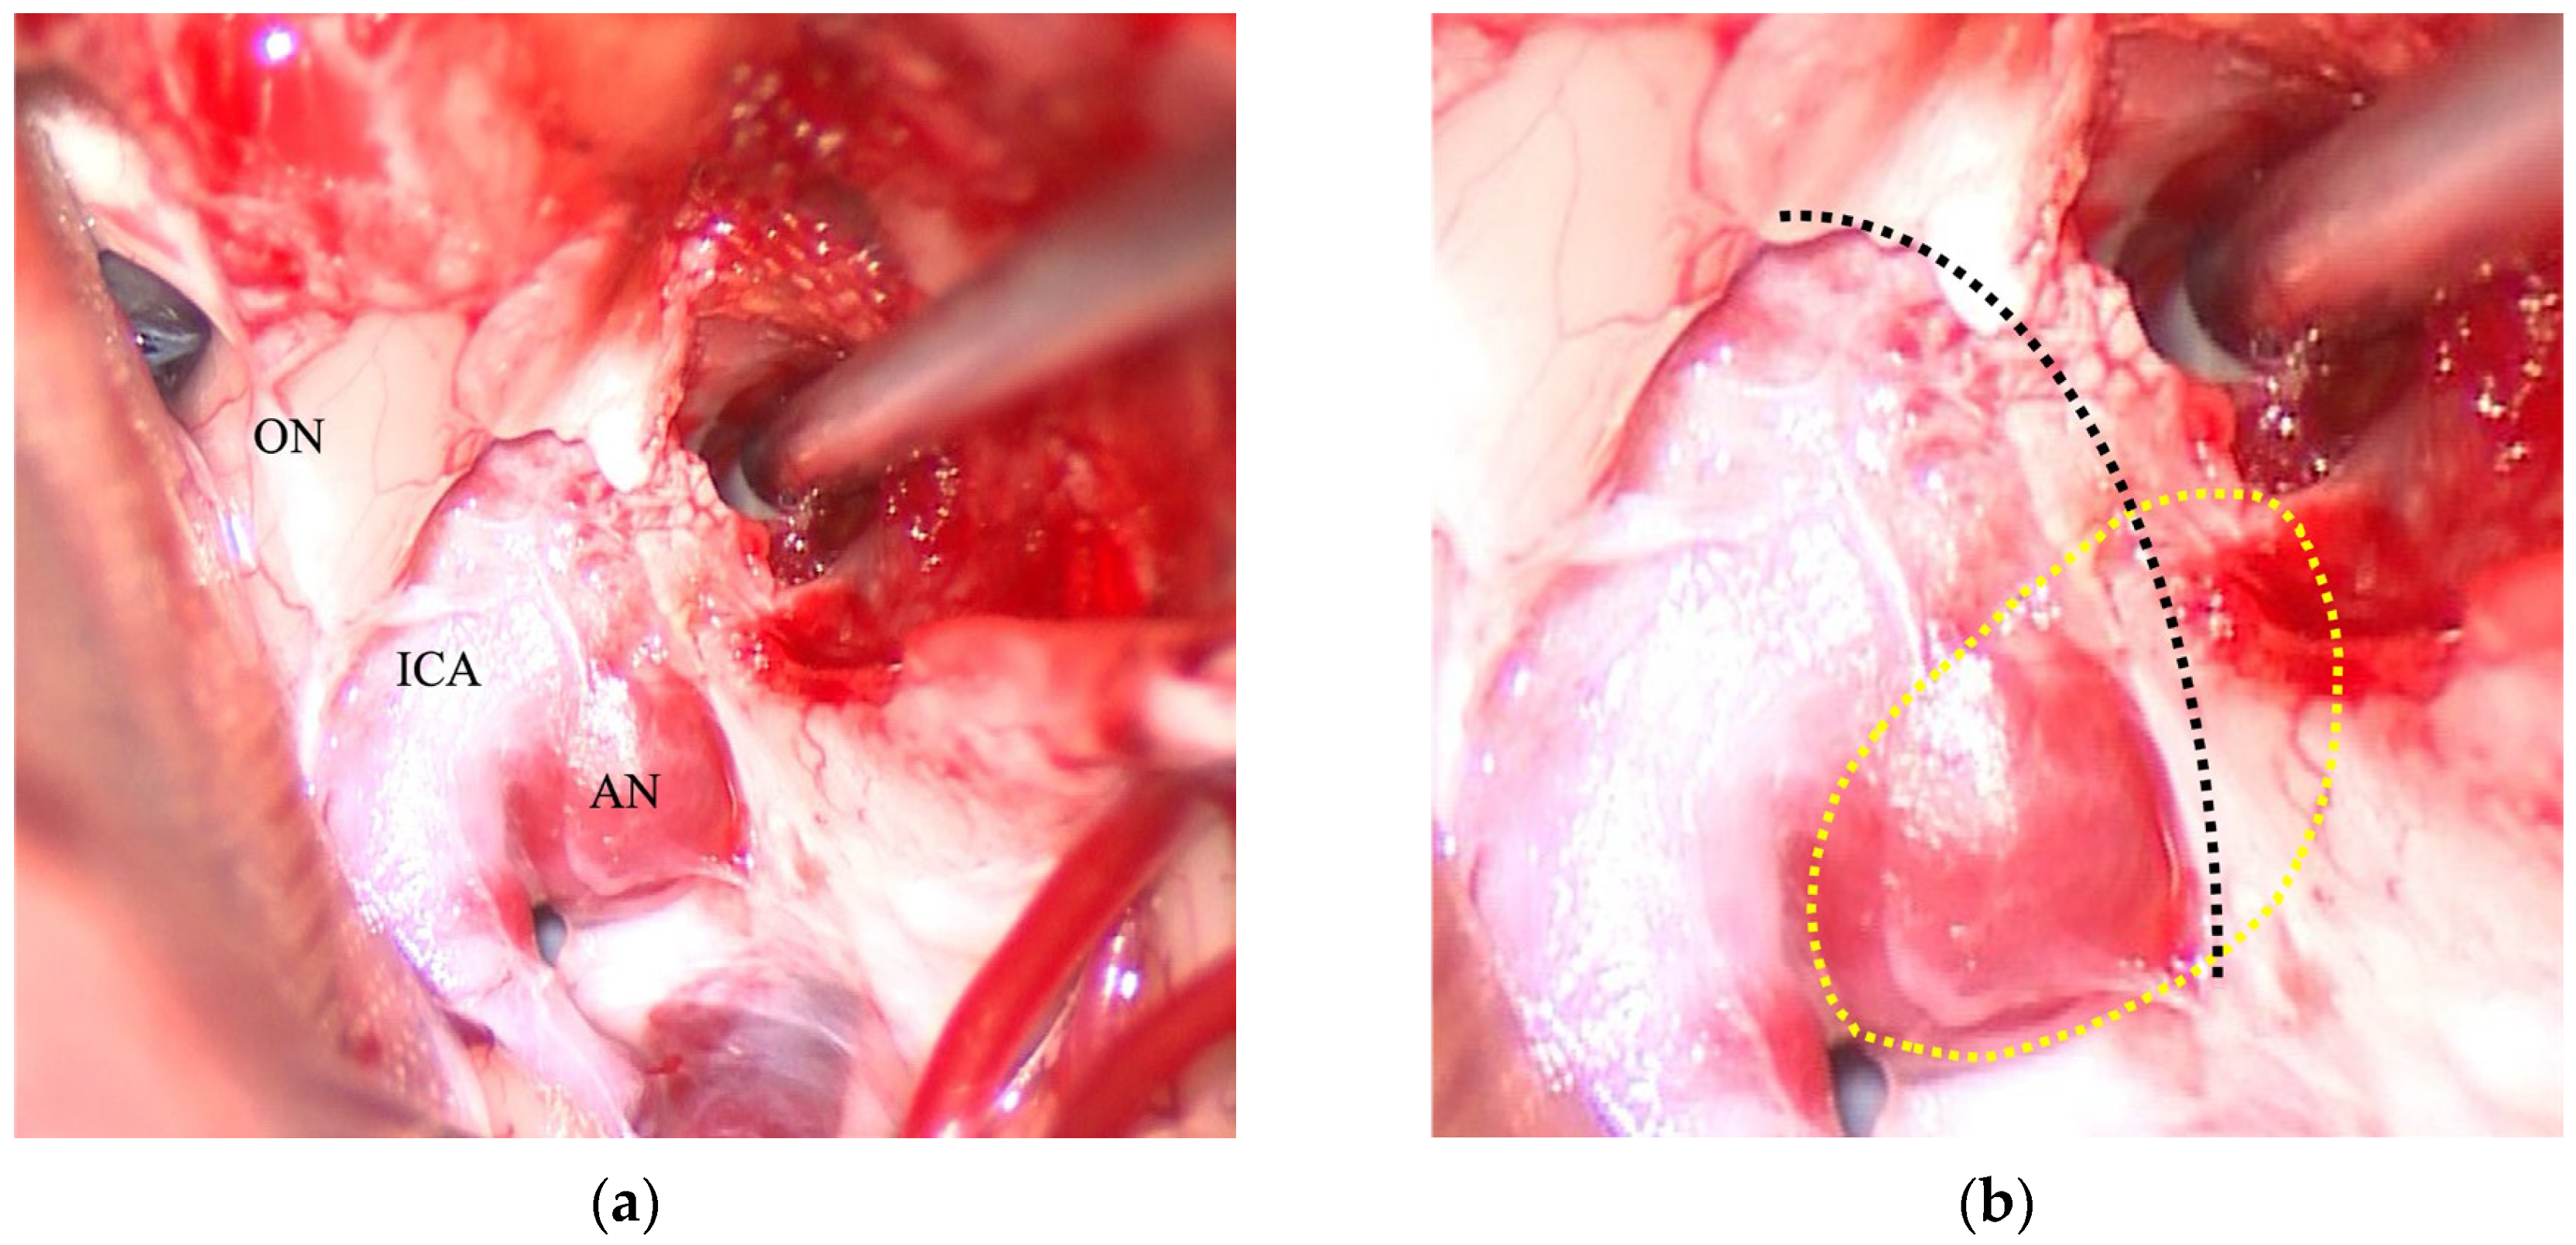

2.2. Surgical Procedure

4.1. Anatomical Basis and Technical Considerations